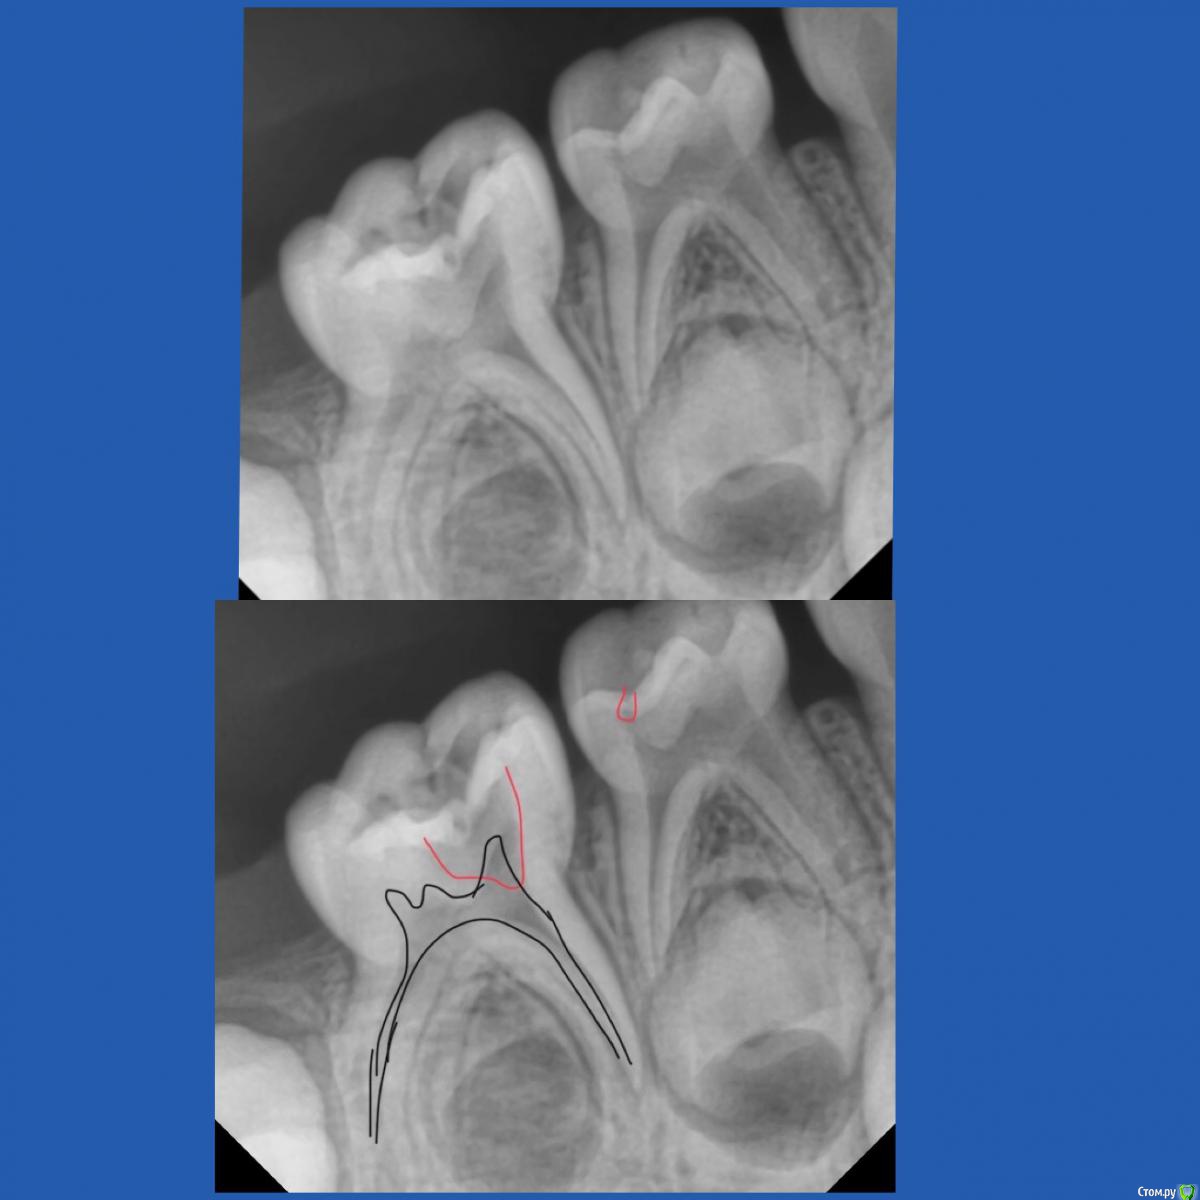

CRAZYDUCK Опубликовано 12 мая, 2018 Автор Поделиться Опубликовано 12 мая, 2018 К предыдущему посту Но предстоящее лечение 8.5 все же сложное и это первый опыт . Как он пройдёт ? Не испугается ли онемения ? «Высидит» ли за один раз все ? Старшая сестричка Вероники очень боится лечить зубы ( с третьего визита позволила только почистить зубы ) . Был Негативный опыт , может повезёт и покажу и сестричку .Вероника молодцом ! Только устала , но выбор подарка после лечения ее взбодрил .Теперь по делу - экстирпация во временных зубах - это глубокая или очень глубокая ампутация. Наша задача удалить нерв , не выходя за апекс временного ( примерно на 2/3 длины канала ), моем гипохлоритом (!!!!) , сушим пылесосом ( можно одеть канюлю от метапекса - метапасты на насадку пылесоса и просушить в канале ( я ещё досушиваю бумажными пинами).Апекслокатор - не нужен ! Главное , чтобы из канала не кровило и было сухо . Инструментальная обработка Sx ( устьевик), потом ручными ( я чаще до 25.02 максимум прохожу ),пломбирую пастой Йодотин ( аналог метапекса), проверяем вне полости рта - идёт ли паста из канюли - вводим в устье , аккуратно выдавливаем - появилась паста в устье - начинаем вытягивать канюлю из канала ( одновременно выдавливая пасту ). Делаем то же самое с другими каналами и убираем излишки . Я перекрываю кальцимолом устья , под коронку восстанавливаю IRM. Фиксация Коронки без коффердама . Излишки цемента из межзубных промежутков убираю флоссом, посередине нитки делаем узелок , чтобы он помог вывести излишки . Фиксирую на айрекс цем .( с дёсны излишки цемента не убрала - устала Вероничка). Ссылка на комментарий